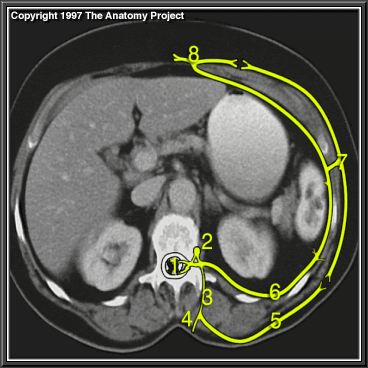

Spinal cord

Sympathetic ganglion

Dorsal ramus

Medial branch of dorsal ramus

Lateral branch of dorsal ramus

Intercostal nerve (ventral ramus)

Lateral cutaneous branch of intercostal nerve

Anterior cutaneous branch of intercostal nerve